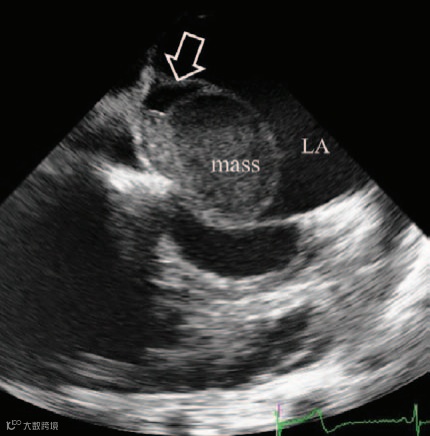

发现一个5.4×3.9厘米的低回声肿瘤,该肿瘤脱垂穿过二尖瓣,导致左心室流入道梗阻(图2;视频I)。肿瘤质地柔软、表面光滑,有蒂起源于房间隔。

图2

显示肿瘤内部有动态烟雾样回声(提示存在自发显影,图3;视频I)。M型超声显示肿瘤在收缩期两次回弹至左心房腔,产生M形信号(图4;视频II),提示肿瘤内部充满液体而非凝血,呈现血球样外观。彩色多普勒显示有血流流入(图5)和流出肿瘤(图6),且主要发生在舒张期(图7和8;视频III),提示血供来源于冠状动脉。